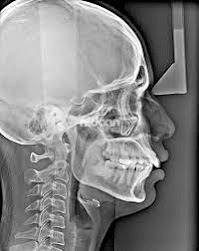

- Cephalometric radiographs are mainly used in orthodontic treatments. It shows the half side of the head in lateral view. The dentist uses this x-ray to determine the malalignment of the teeth and the jaw bones.